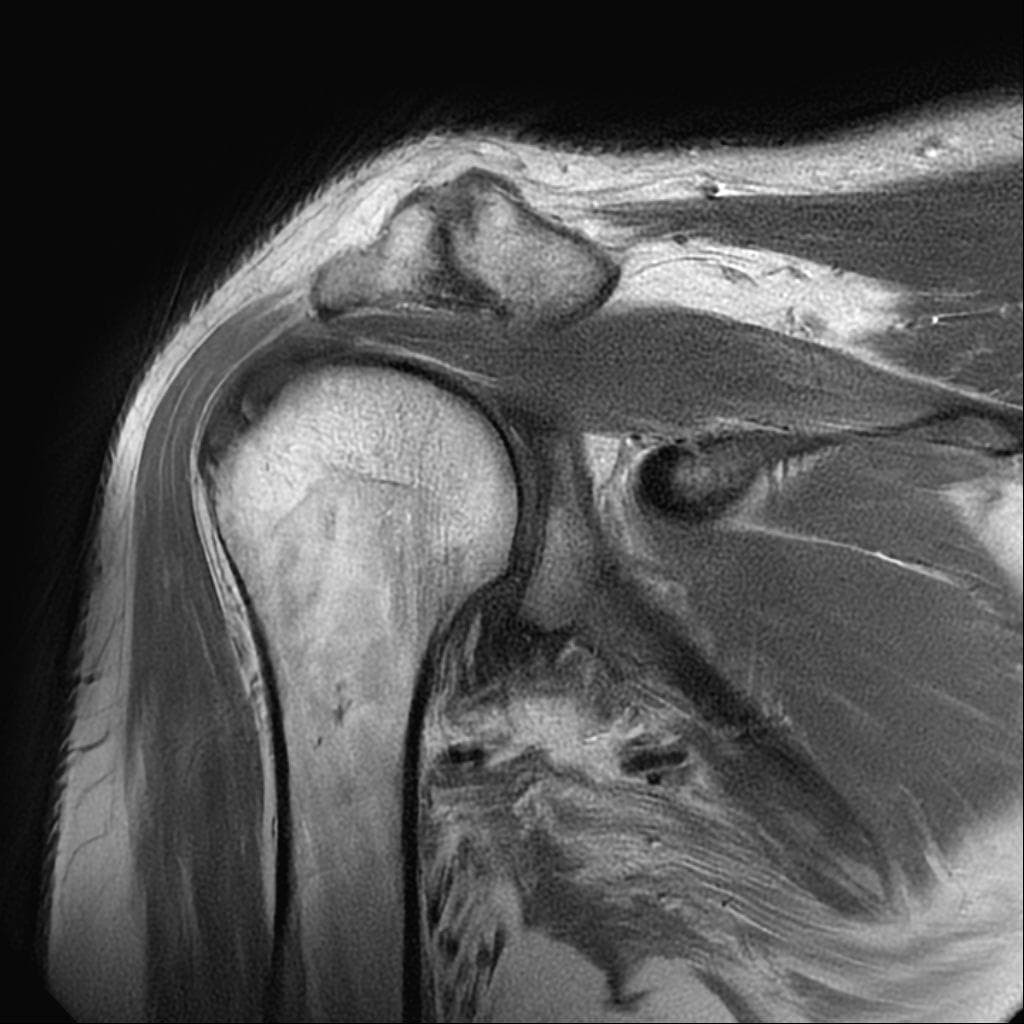

어깨 mri 상태인데 어디가 안 좋은가요?

해당사진으로 많은걸확인할수는없지만 회전근개손상을 의심해볼수있는데요 지속적으로 불편감이있다면 병원에서 검사와치료를받아보시길 바랍니다 감사합니다~

제가 직접 mri를 판독할 수는 없지만 일반적으로 어깨 mri에서 이상 소견이 자주 지적되는 부위는 회전근개 힘줄에 염증, 부분 파열, 손상이 흔합니다 또 견봉 아래 공간으로 충돌증후군이나 염증으로 공간이 좁아질 수 있습니다. 관절순은 탈구 벼력이 있으면 손상 가능성이 있어요 정확한 위치와 정도는 영상의학과 판독결과와 주치의 설명을 참고해야 합니다!

현재로썬 사진만으론 판단을 하긴 어렵지만 회전근개의 손상이 의심 갑니다.

회전근개 주변의 염증이나 손상이 발생하신 것으로 유추해볼 수 있겠습니다.

회전근개 손상은 어깨 관절 주변의 통증과 움직임 제한이 발생할 수 있으며,

완전 파열이 아닌 경우에는 보존적 치료를 우선 적용할 수 있습니다.